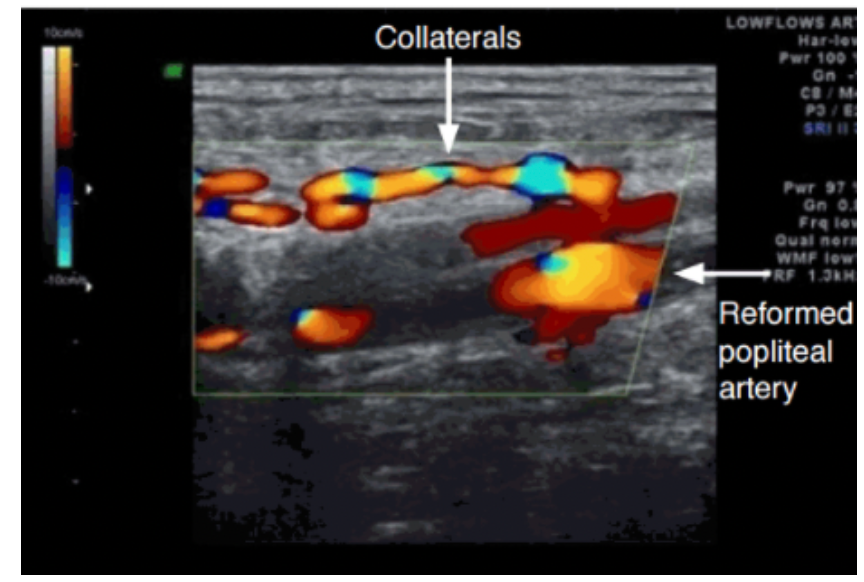

Which arterial abnormality is most consistent with the ultrasound image below? Keep in mind this is demonstrating obstruction with collateralization.

1. Chronic atherosclerotic obstructive disease

2. Acute arterial occlusion

3. Arteriovenous fistula

4. Pseudoaneurysm

A